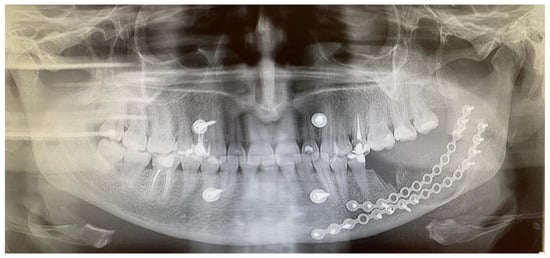

Figure 4. An immediate early panoramic radiograph with very good and stable outcomes. After tumor removal, ostectomy, local resection, and reconstruction with allogenic bone graft and titanium plates, the result is very good. Because a very thin healthy bone layer was remaining, additional IMF—intramaxillary—screws (titanium 2.0 plates, Medartis, Basel, Switzerland) were used to maintain stable occlusion, avoid any fracture, and decrease the possibility of any wound dehiscence and irritation. It is worth noting and remembering that CGCG should be differentiated from the following lesions and tumors: brown tumors in PHP, peripheral form of CGCG (PGCG), giant cell tumor, lesions from cherubism, non-ossifying fibromas, and ABCs—aneurysmal bone cysts—or even ameloblastoma [4,5]. Radiological differentiation should also include myxoma/odontogenic-myxoma (OM), ameloblastic fibroma (AF), and ossifying fibroma (OsF); however, the additional presence of calcifying and bone masses inside the lesions, with an irregular border and lesion shape, improves the diagnosis. Some atypical cyst formation, spread, and occurrence in the jaw bone might also mimic other tumors or lesions, which is why it is crucial to evaluate each atypical case carefully [6]. This case underlines how similar radiological appearances can be seen in various different tumors, and how not only a biopsy but bone makers with SPECT examination can improve the diagnostics. Each BT and CGCG can be misdiagnosed, which is why improved histopathology is important w a larger sample. This case excluded PHP; however, more extensive histopathological evaluation concluded an occurrence of typical brown tumor characteristics for a long but slow growth, but without any significant correlation between the endocrine and calcium–phosphate markers, which is quite unusual.